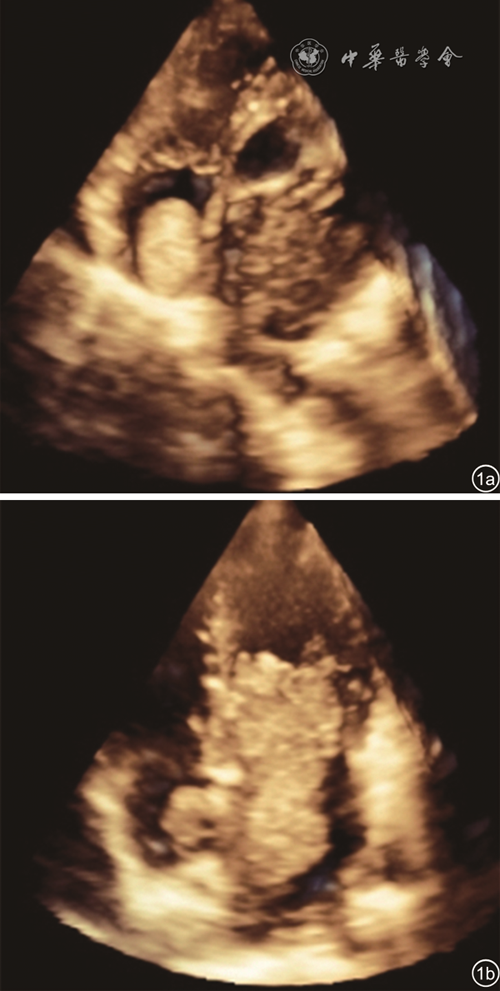

图1 心脏黏液瘤超声心动图图像。图a示右心房黏液瘤;图b示左心房黏液瘤